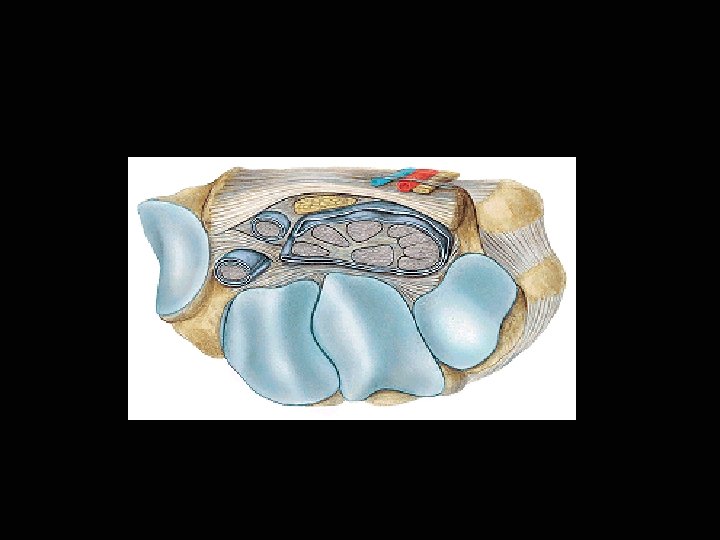

Средно фасциално леговище Сухожилно-мускулен слой: - mm. flexores digitorum superficialis et profundus - mm. lumbricales - vagina synovialis communis flexorum Две съединителнотъканни пространства а. Повърхностно - под дланната апоневроза - arcus palmaris superficialis - aa. digitales palmares communes - n. medianus - nn. digitales palmares communis - r. palmaris n. ulnaris - n. digitalis palmaris communis IV и n. digitalis palmaris proprius V Междуфасциални канали - дистално от пространството - mm. lumbricales, a. n. palmares digitales comm. et propriae

Средно фасциално леговище б. Дълбоко (подсухожилно) пространство под fascia palmaris interossea - комуникации: предмишница - проксимално през canalis carpi повърхностно простронство - междуфасциални канали - arcus palmaris profundus - a. radialis + r. profundus a. ulnaris - aa. metacarpales palmares - aa. digitales palmares communes - дълбок клон на r. palmaris n. ulnaris за: - mm. hypothenari, mm. interossei, m. adductor pollicis и mm. lumbricales II - IV.